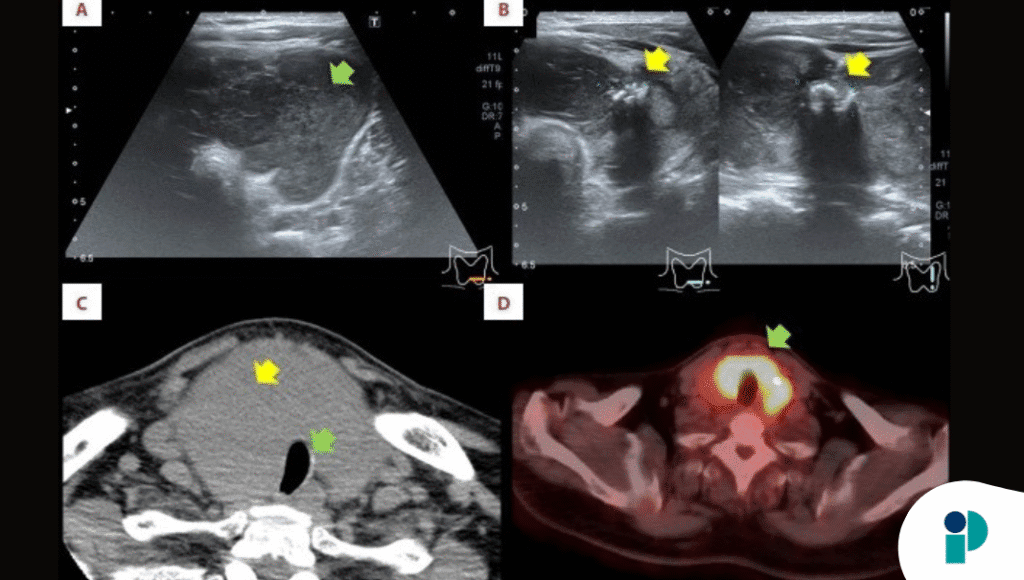

Inicialmente, los médicos se enfrentaron a la dificultad de discernir la causa de la inflamación de los ganglios linfáticos del cuello y la captación de F-fluorodesoxiglucosa cerca del páncreas, un hallazgo en la tomografía por emisión de positrones (TEP).

No estaba claro si estas anomalías estaban vinculadas al CPT, al linfoma maligno o a ambos. Este caso ilustra los desafíos diagnósticos que pueden surgir cuando múltiples patologías se superponen.

Para abordar las afecciones, se realizó una tiroidectomía total y una disección de ganglios linfáticos. Tras el análisis histopatológico, se confirmó el diagnóstico de CPT y linfoma MALT, atribuyéndose la inflamación de los ganglios linfáticos al linfoma MALT.